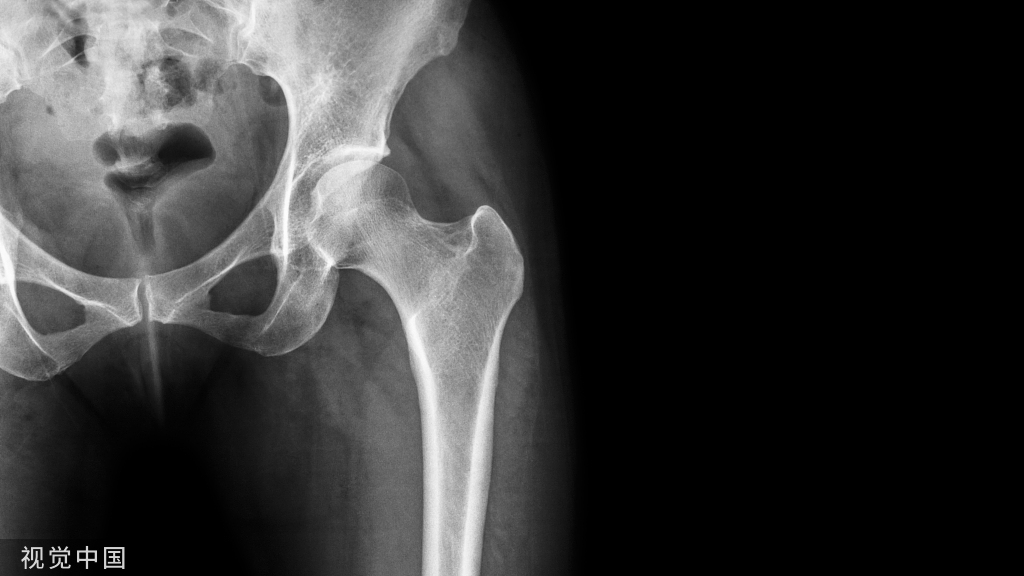

从长骨干取除断裂的髓内钉仍然是一个棘手的问题。本文介绍一种方法,该方法在技术上比文献中描述的其他方法要求低。此方法类似于钓鱼,这是一种通过鱼钩钓鱼的方法。在这种方法中,断裂的钉子在透视引导下钩住,并通过由不锈钢丝制成的钉钩以逆行方式取回。它无创地去除断裂的钉子,需要进一步暴露。1.首先钩子有一个宽阔的嘴,一个窄的弯曲(图A,B)。

钓鱼技术用于取回髓内钉远端断裂部分。取了一根 20 号长的不锈钢线,其长度足以到达并取回断裂的钉子。如上所述,在其一端制作了一个钉钩。将去除的钉子近端部分用作模板,以按照所需的尺寸制作钩子。在透视引导下,钩子沿着髓管向下传递,然后穿过断裂的钉子,使得整个钩子位于钉子远端()。

然后将不锈钢丝拉近端以钩住断裂的钉子。然后通过轻轻地将不锈钢线拉出来取回钉子(图B)。